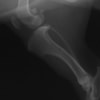

術後左後肢側面像

手術は片足ずつ行い、両膝とも術中の関節鏡検査にて前十字靭帯の完全断裂と半月板損傷を確認しました。TPLO、半月板切除と滑車溝形成を始めとした膝蓋骨脱臼整復術を実施いたしました。膝蓋骨の安定化を測るために外側支帯を強固に縫合し、内側支帯は切除し縫合せずに開放状態にしています。

術後の歩行状態は良好です。

術前のTPAは左後肢33.1°右後肢26.8°でしたがTPLO実施により左後肢5.5°右後肢12°に矯正されました。